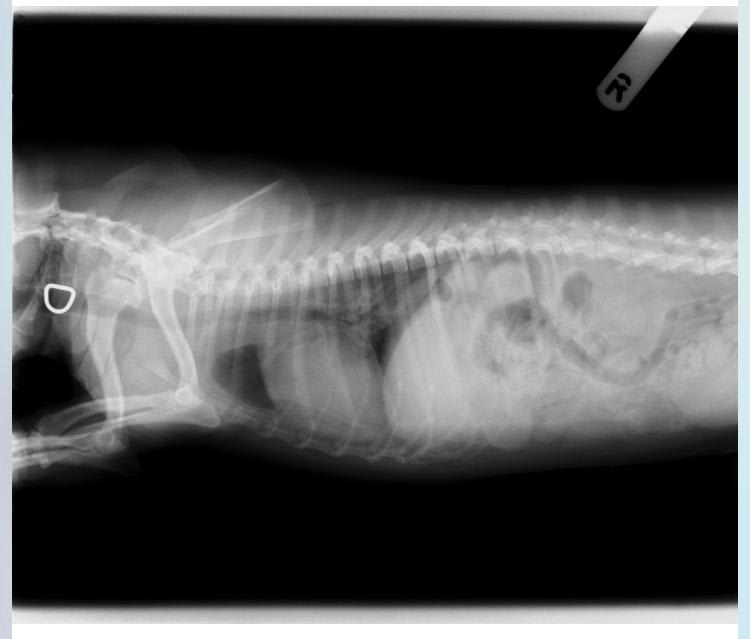

I agree that Duke heart looks enlarged and it is pushing up on his trachea. I cannot diagnose his condition without doing an exam but with just looking at the X-rays, I would say he definitely has a heart condition. I have heard coughs from heart problems sound very similar to upper respiratory infections. Your vet will be able to put him in some heart medicine to help him. Heart medicine will slow down the progression of heart disease and help him feel better. I hope this helps. I'm sorry for the news!

Coughing can indeed be caused by kennel cough infection but it can also be caused by heart disease. In the above radiography the heart looks enlarged and seems to be pushing up the trachea. This can lead to trachea sensitivity which can cause a bad cough. A diagnosis of heart disease is made on clinical signs, listening to the chest along with diagnostic imaging. I would imagine that your vet is correct in this instance. Treatment involves administering tablets to increase the heart output, control fluid in the chest and control kidney involvement. Your vet will be able to make you a treatment plan.